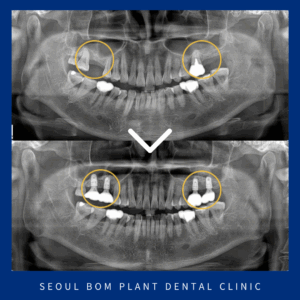

오륜동치과 상악동 거상술을 동반하여

오륜동치과 상악동 거상술을 동반하여 안녕하세요. 서울봄플란트치과 대표원장 송원섭입니다. 치아는 이동하려고 하는 성질이 있어 치아를 상실하게 된다면 빈 공간으로 치열이 이동하면서 전체적으로 비정상적인 위치를 가지게 되는데요. 이렇게 되면 제대로…